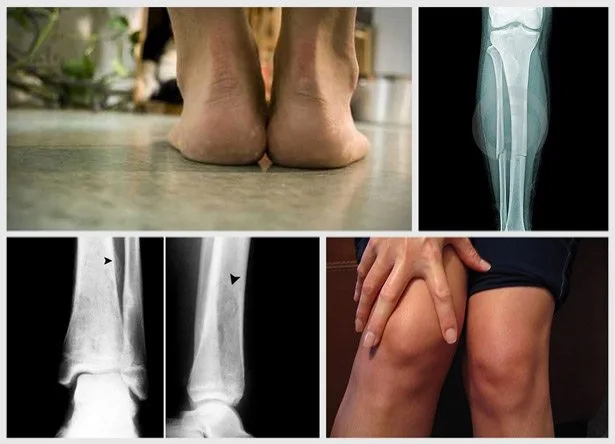

Bol u potkolenici

Gde: bol koji se javlja celom dužinom potkolenice, to je mikro fraktura tibialne kosti (cevanice).

Rizična grupa: trkači koji trče sa vrhovima stopala okrenutim ka spoljnoj strani (pronatori), početnici, žene koje nose visoke potpetice i svi oni koji treniraju na kosim terenima.

Zašto: zato što prednja tibialna tetiva mora da daje veliki otpor rotirajućem stopalu i tako trpi veliki pritisak.

Kako da sprečite: nosite patike koje odgovaraju vašem stilu gaženja, one će bolje kontrolisati pokret vaših stopala, ojačajte listove na nogama. Ako imate bolove u potkolenici duže od mesec dana idite kod doktora na snimanje da biste proverili kakva je fraktura u pitanju.

Sindrom bola oko celog kolena

Gde: bol i ukočenost oko čašice kolena.

Rizična grupa: žene koje trče sporim tempom, pronatori i ljudi sa ravnim stopalima.

Zašto: u idealnim uslovima čašica kolena klizi gore dole pri svakom savijanju i udaru. Žene imaju mnogo fleksibilnije zglobove i prave veće uglove (kuk-koleno) od muškaraca, pa tako imaju veće šanse da im čašica ispadne jer ligamenti neće dobro držati pri takvim uglovima i sporom trčanju.

Kako da sprečite: ojačajte prednju ložu, zadnju ložu i zadnjicu sa čučnjevima, iskoracima, jer će jači mišići pomoći pri stabilizaciji čašice kolena kao i držanju karlice u pravilnom položaju dok trčite.